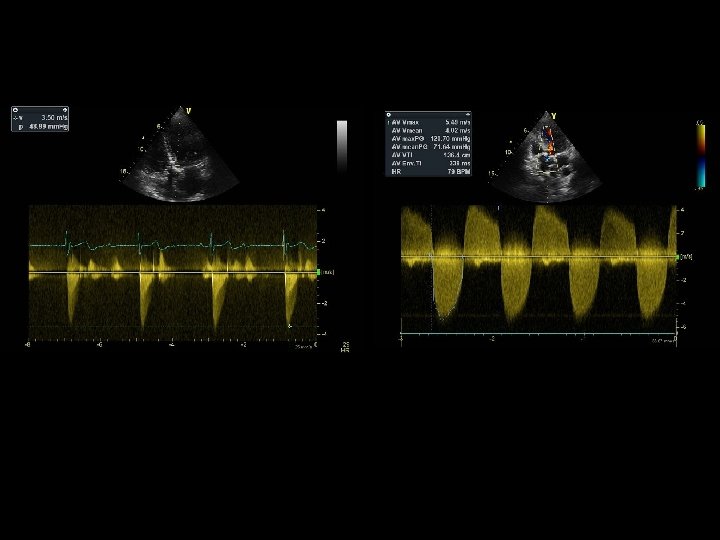

SEVERE AS Mean gradient = 71 mm Hg Dimensionless index = 0. 5 / 5. 5 = 0. 1

AORTIC STENOSIS Severity Parameters sclerosis mild AS moderate severe Vmax. . m/sec < 2. 5 2. 6 – 2. 9 3. 0 – 3. 9 ≥ 4. 0 MPG mm Hg -- < 20 20 – 39 ≥ 40 AVA cm 2 -- > 1. 5 1. 0 – 1. 5 < 1. 0 AVAI cm 2 / m 2 -- > 0. 85 0. 6 – 0. 85 < 0. 6 Dimensionless index -- > 0. 5 0. 25 – 0. 5 < 0. 25